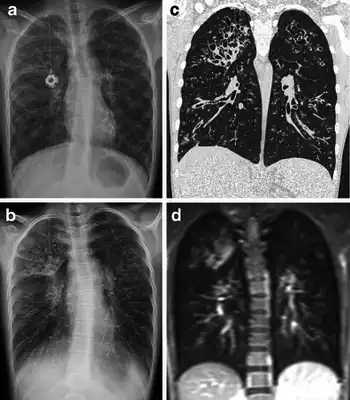

a-d)Cystic fibrosis (a degenerative disease) via radiography, tomosynthesis, CT and MRI